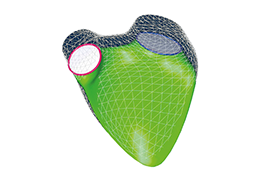

Performs 3D reconstruction and volume rendering.

Instant and interactive surface extraction and export to STL and PLY formats.